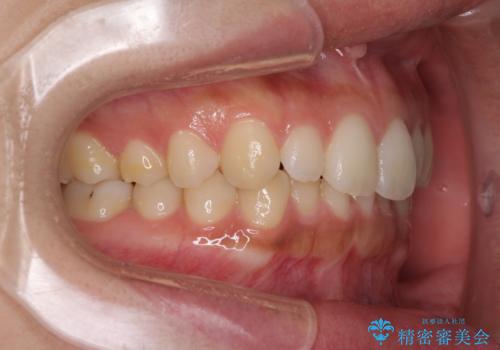

- 前歯のデコボコを気にして来院された患者様です。

通常であれば半年から10ヶ月程度で終了する歯並びでしたが、海外に長期出張することになったため、1年10ヶ月の期間を要しました。

出張に行かれてしまうと追加のマウスピースを発注できないため、マウスピースの交換頻度を低くし、一時帰国のタイミングに合わせていくことで、スムーズに進めて行くことができました。